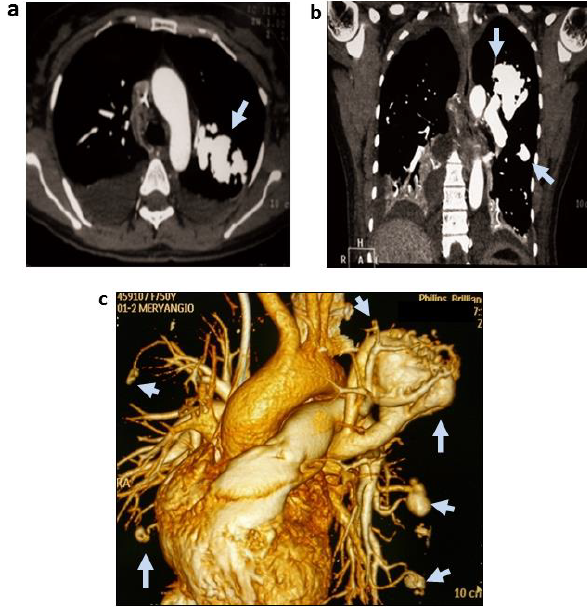

Así mismo, se observaron múltiples telangiectasias con opacificación difusa y anormal de la mucosa nasal con irrigación aferente distal de arterias pterigopalatinas (figuras 2a y 2b). La arteriografía cerebral digital con reconstrucciones 3D en carótida interna izquierda, demostró aneurisma sacular roto bilobulado de 6 mm y cuello amplio a nivel de arteria comunicante anterior (ACoA) (figura 2c). En vista de estos hallazgos angiográficos que sugerían ruptura reciente del aneurisma de ACoA, la paciente fue tratada en estado clínico agudo con técnica endovascular de embolización con micro coils, ocluyendo la lesión completamente, sin complicaciones.

Adicionalmente, durante su hospitalización se le practicó tomografía computarizada de tórax con contraste, reconstrucciones multiplanares axiales (figura 3a), coronales (figura 3b) y reconstrucción 3D (figura 3c); demostraron múltiples MAV pulmonares bilaterales, con lesión dominante y prominente en lóbulo superior izquierdo, así como también derrame pleural bilateral, más acentuado del lado derecho.